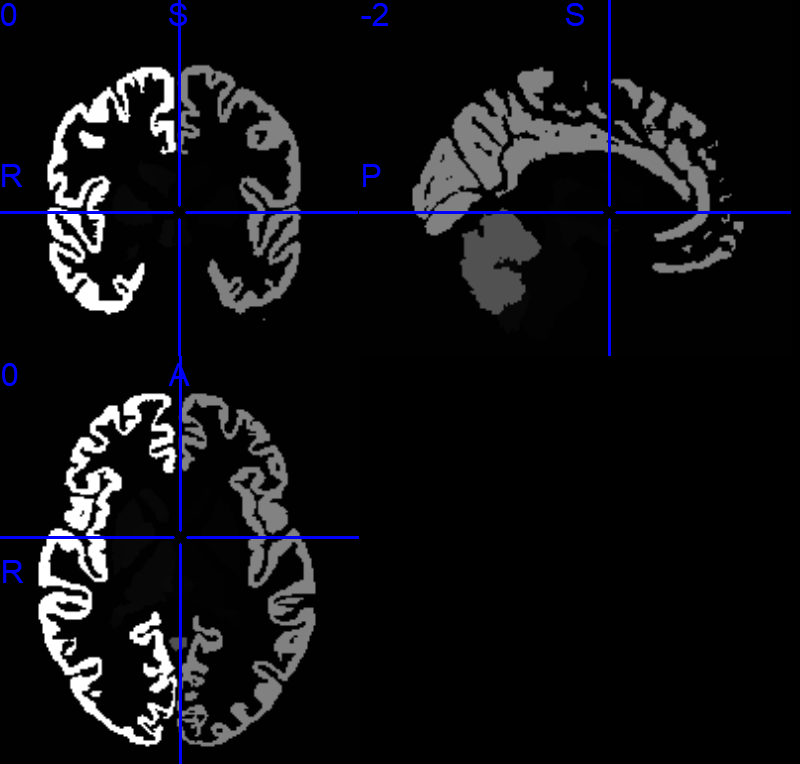

老师您好,我也是想把DK图谱的脑区映射到Yeo 7子网络中,您推荐的这个项目中,给了很多图谱文件,Yeo 7图谱应该是Yeo-7_space-MNI152NLin6_res-1x1x1.nii.gz这个文件,但我不知道常用的DK图谱(包含68个脑区的)是哪一个,烦请老师指教。文件夹中有Desikan_space-MNI152NLin6_res-1x1x1.nii.gz、DesikanKlein_space-MNI152NLin6_res-1x1x1.nii.gz和DKT_space-MNI152NLin6_res-1x1x1.nii.gz三个文件,在MRIcron中打开分别如下:

-